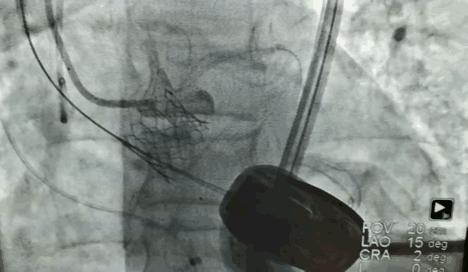

67岁女性,主动瓣左冠窦腔小,严重钙化,主动脉宽,冠状动脉开口位置低,手术条件恶劣。

冠状动脉开口位置的高度相对较低,是决定病人能不能做TAVR手术的非常重要的因素。如果冠状动脉开口比较低,有可能瓣膜植入之后会挡住冠状动脉开口,引起急性心梗,这将是一个灾难性的后果。

术前就和周玉杰教授团队做了周密研讨和细致评估,包括体外模拟植入瓣膜后的冠脉情况。术中,也做了多种应急预案,一方面备了体外循环机器,万一不行,就转机上体外循环支持;另一方面,在左冠主干的位置放了导丝,如果造成左冠动脉缺血,会立即行冠状动脉球囊扩张➕支架植入治疗。

在瓣膜的选择上,也充分考虑到冠脉开口位置低、主动瓣左冠的窦部比较小的问题,最终采用16mm球囊预扩,20mm瓣膜释放,一个半小时左右的手术过程顺利,冠状动脉开口没有受到影响,冠脉的供血也比较好。

可以说,这台的成功得益于术前充分的会诊、讨论、风险评估,防止一切发生风险的因素,这不仅仅是一台高难度手术,更是多学科协作的成功典范。